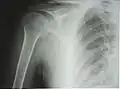

Рентгенограмма верхней части плечевой кости с выраженной хирургической шейкой